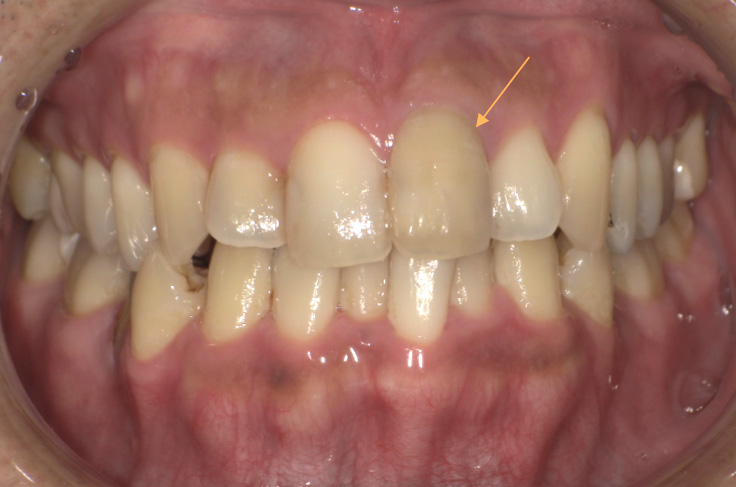

治療前の写真

治療後の写真

| 主訴 | 左上の1番の歯の色味が気になる |

|---|---|

| 治療期間 | 約1か月 |

| 治療費 | 1回¥5,500×3回 (約1~2週間で薬剤交換) |

| 治療内容 | ウォーキングブリーチという治療です。 神経がない歯の内部に薬剤を入れ内側から白くしていく方法です。 色味を確認しながら薬剤を交換し色味が納得できたタイミングで穴を封鎖します。 |

| 治療のリスク | 白さが後戻りすることがあります。色味の変化に個人差があります。 歯質が脆い場合や残っている歯の量が少ない場合には、ウォーキングブリーチは適応となりません。その場合は、歯を保護し形態を修復することができるクラウンが適応となります。 妊娠中や未成年の方、無カタラーゼ症の方・根の病変がある場合は、ウォーキングブリーチは行うことができません。 |